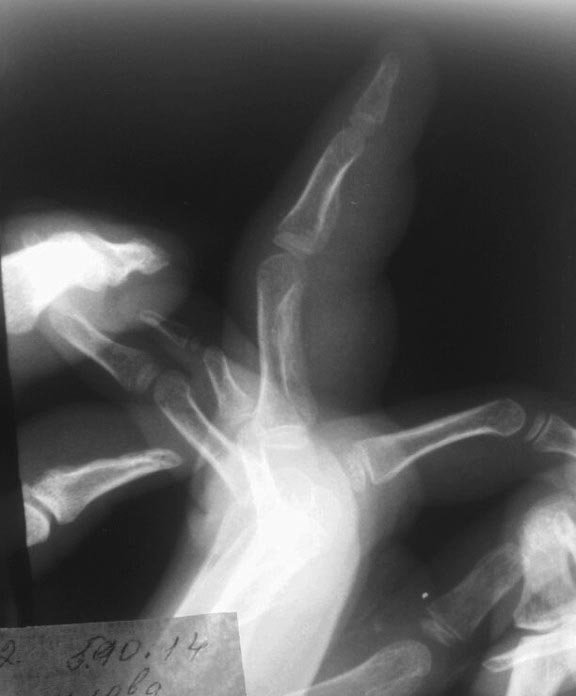

Ребенок 4 года в конце апреля прищемил палец стулом. Через 2 недели

палец стал опухать. Через месяц в июне они пришли, сделали рентген -

ничего нет. Они ничего не делали (то мазали, то не мазали разными

мазями). В июле опять пришли с таким же пальцем ни чуть не изменился.

Сделали рентген - какая-то реакция надкостницы слабовыраженная у

основания основной фаланги 3п кисти. Узи сделали - типа гематома м/тк

после травмы. Все посмотрели (хирурги, рентгенологи и травматологи). Все

дружно решили - гематома, лимфостаз, надо компрессики, массажи,

ванночки, помазюкать и все пройдет. Пришли на этой недели (5 месяцев

после травмы) - всё тоже, не прошло, палец только толще. Рентген -

какая-то штука выросла у основной фаланги и лезет на среднюю. На узи

усиленный кровоток в сухожилии сгибателя и отек сухожильного влагалища

на всем протяжении. Сделали ОАК - без патологии, б/х (о.белок,

билирубин, аст, алт, амилаза, мочевина, креатинин, К, Na, Ca) - без

патологии, на ЩФ - нет реактива в лаборатории.

Палец не болит, сгибается, цвет кожи не особо изменен. Отек плотный.

Движения в полном объёме, только в межфаланг.суст чуть ограничены из-за

сильного отека. Ребенка этот палец совсем не беспокоит. Что это может

быть? и какие дополнительные обследования необходимы?